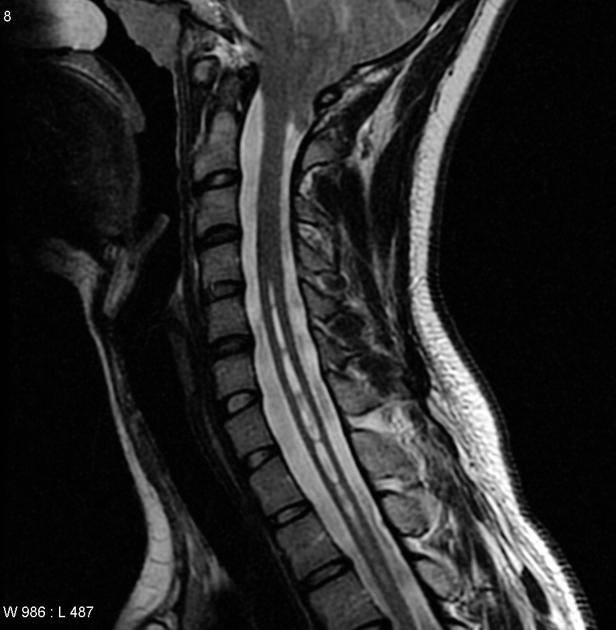

Diagnosis?

Chiari 1. Caudal extension of the cerebellar tonsils 5 mm below the foramen magnum. Syringomyelia seen in 50%.

Associated with: shortening of the clivus, basilar invagination, C1 assimilation, and fused cervical vertebrae (Klipper-Feil syndrome).